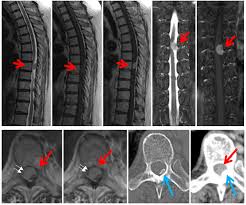

脊髄腫瘍 硬膜外腫瘍 硬膜内髄外腫瘍 髄内腫瘍 馬尾腫瘍など 東京医ç§'æ­¯ç§'大学 整形外ç§'

脊髄腫瘍 硬膜外腫瘍 硬膜内髄外腫瘍 髄内腫瘍 馬尾腫瘍など 東京医ç§'æ­¯ç§'大学 整形外ç§' from tmdu-orth.jp